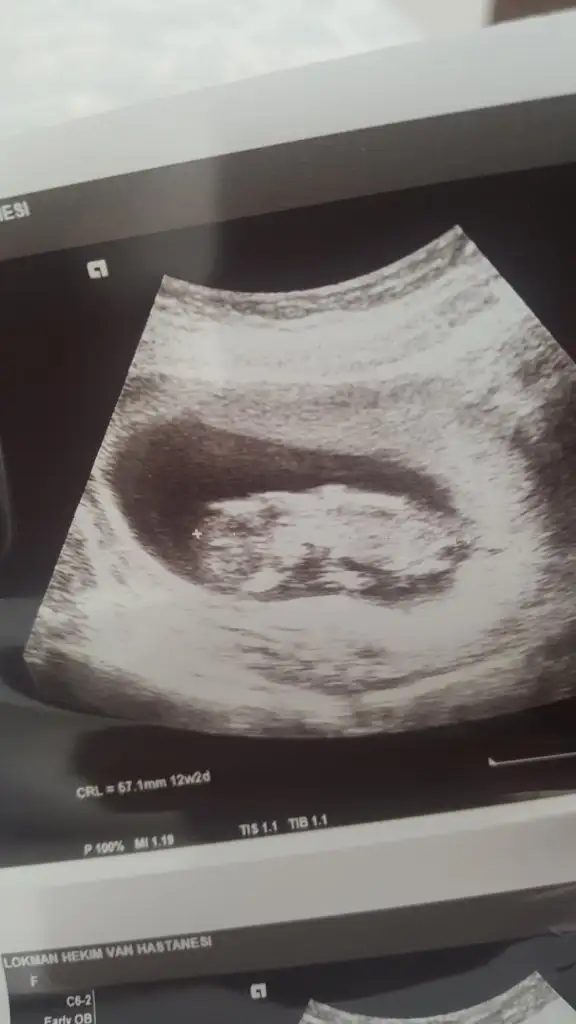

En net olanı bu malesef başka yok. Doktor erkeğe benzetti ama 1 ay sonra kesinleşir dedi. Yorumunuz için teşekkürler hayırlısı olsun :)Bebek hafif yan pozisyonda emin olmamakla birlikte sanki kız tekrar usg paylaşın

Dogrudur o zamam emin olamadım nubu ne dik nede paraleldi bebek yan pozisyonda olunca emin olamadım başka usg ile teyit etmek istemiştim hayırlısı olsun sizin içinEn net olanı bu malesef başka yok. Doktor erkeğe benzetti ama 1 ay sonra kesinleşir dedi. Yorumunuz için teşekkürler hayırlısı olsun :)

Bunada bakabilir misin :)Dogrudur o zamam emin olamadım nubu ne dik nede paraleldi bebek yan pozisyonda olunca emin olamadım başka usg ile teyit etmek istemiştim hayırlısı olsun sizin için

Erkek gibiBir başka ultrason istemiştiniz bunlar var elimde bacaklarini bağlamışti öylece duruyorduheyecanla yorumunuzu bekliyorumm Ikra meyra